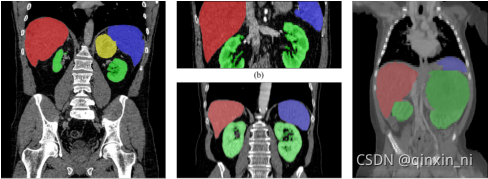

本文主要研究腹部CT扫描的多器官分割。如图所示,主要难点来自四个方面:

- 不同器官的视场、形状和大小的差异。

- 病变器官等异常可能导致分割失败。

- 多中心、多阶段、多厂商案例的数据源多样性。

- GPU内存大小有限,计算成本高。